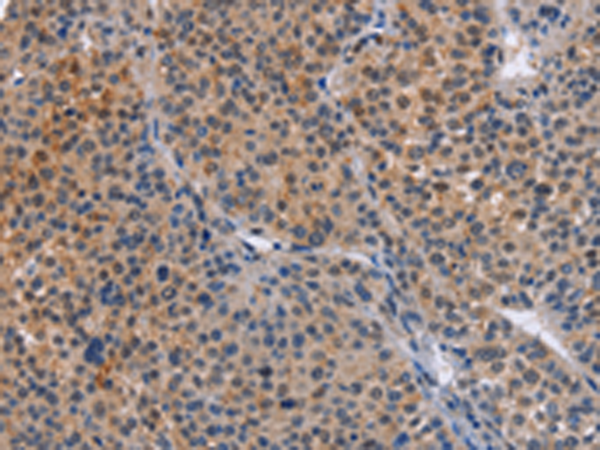

分类: 科研抗体货号: P07986别名: HK; HKD; HKI; HXK1; RP79; HMSNR; HK1-ta; HK1-tb; HK1-tc; hexokinase; HKII; HXK2应用: WB,IHC反应种属: Human, Mouse, Rat